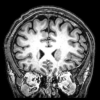

When you're expecting something -- like the meal you've ordered at a restaurant -- or when something captures your interest, unique electrical rhythms sweep through your brain. These waves are called gamma oscillations and they reflect a symphony of cells -- both excitatory and inhibitory -- playing together in an orchestrated way. Though their role has been debated, gamma waves have been associated with higher-level brain function, and disturbances in the patterns have been tied to schizophrenia, Alzheimer's disease, autism, epilepsy and other disorders.